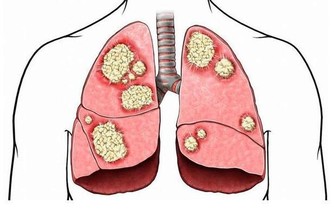

6、康復中的病人